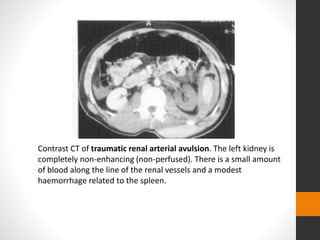

Contrast CT of traumatic renal arterial avulsion. The left kidney is

completely non-enhancing (non-perfused). There is a small amount

of blood along the line of the renal vessels and a modest

haemorrhage related to the spleen.